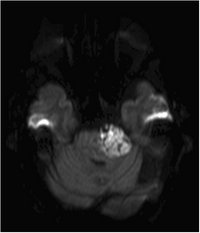

Epidermoid - DWI - axial

Fehlendes Liquorsignal als Signalsteigerung

DD: Arachnoidalzyste, mit  Liquorsignal in allen Sequenzen